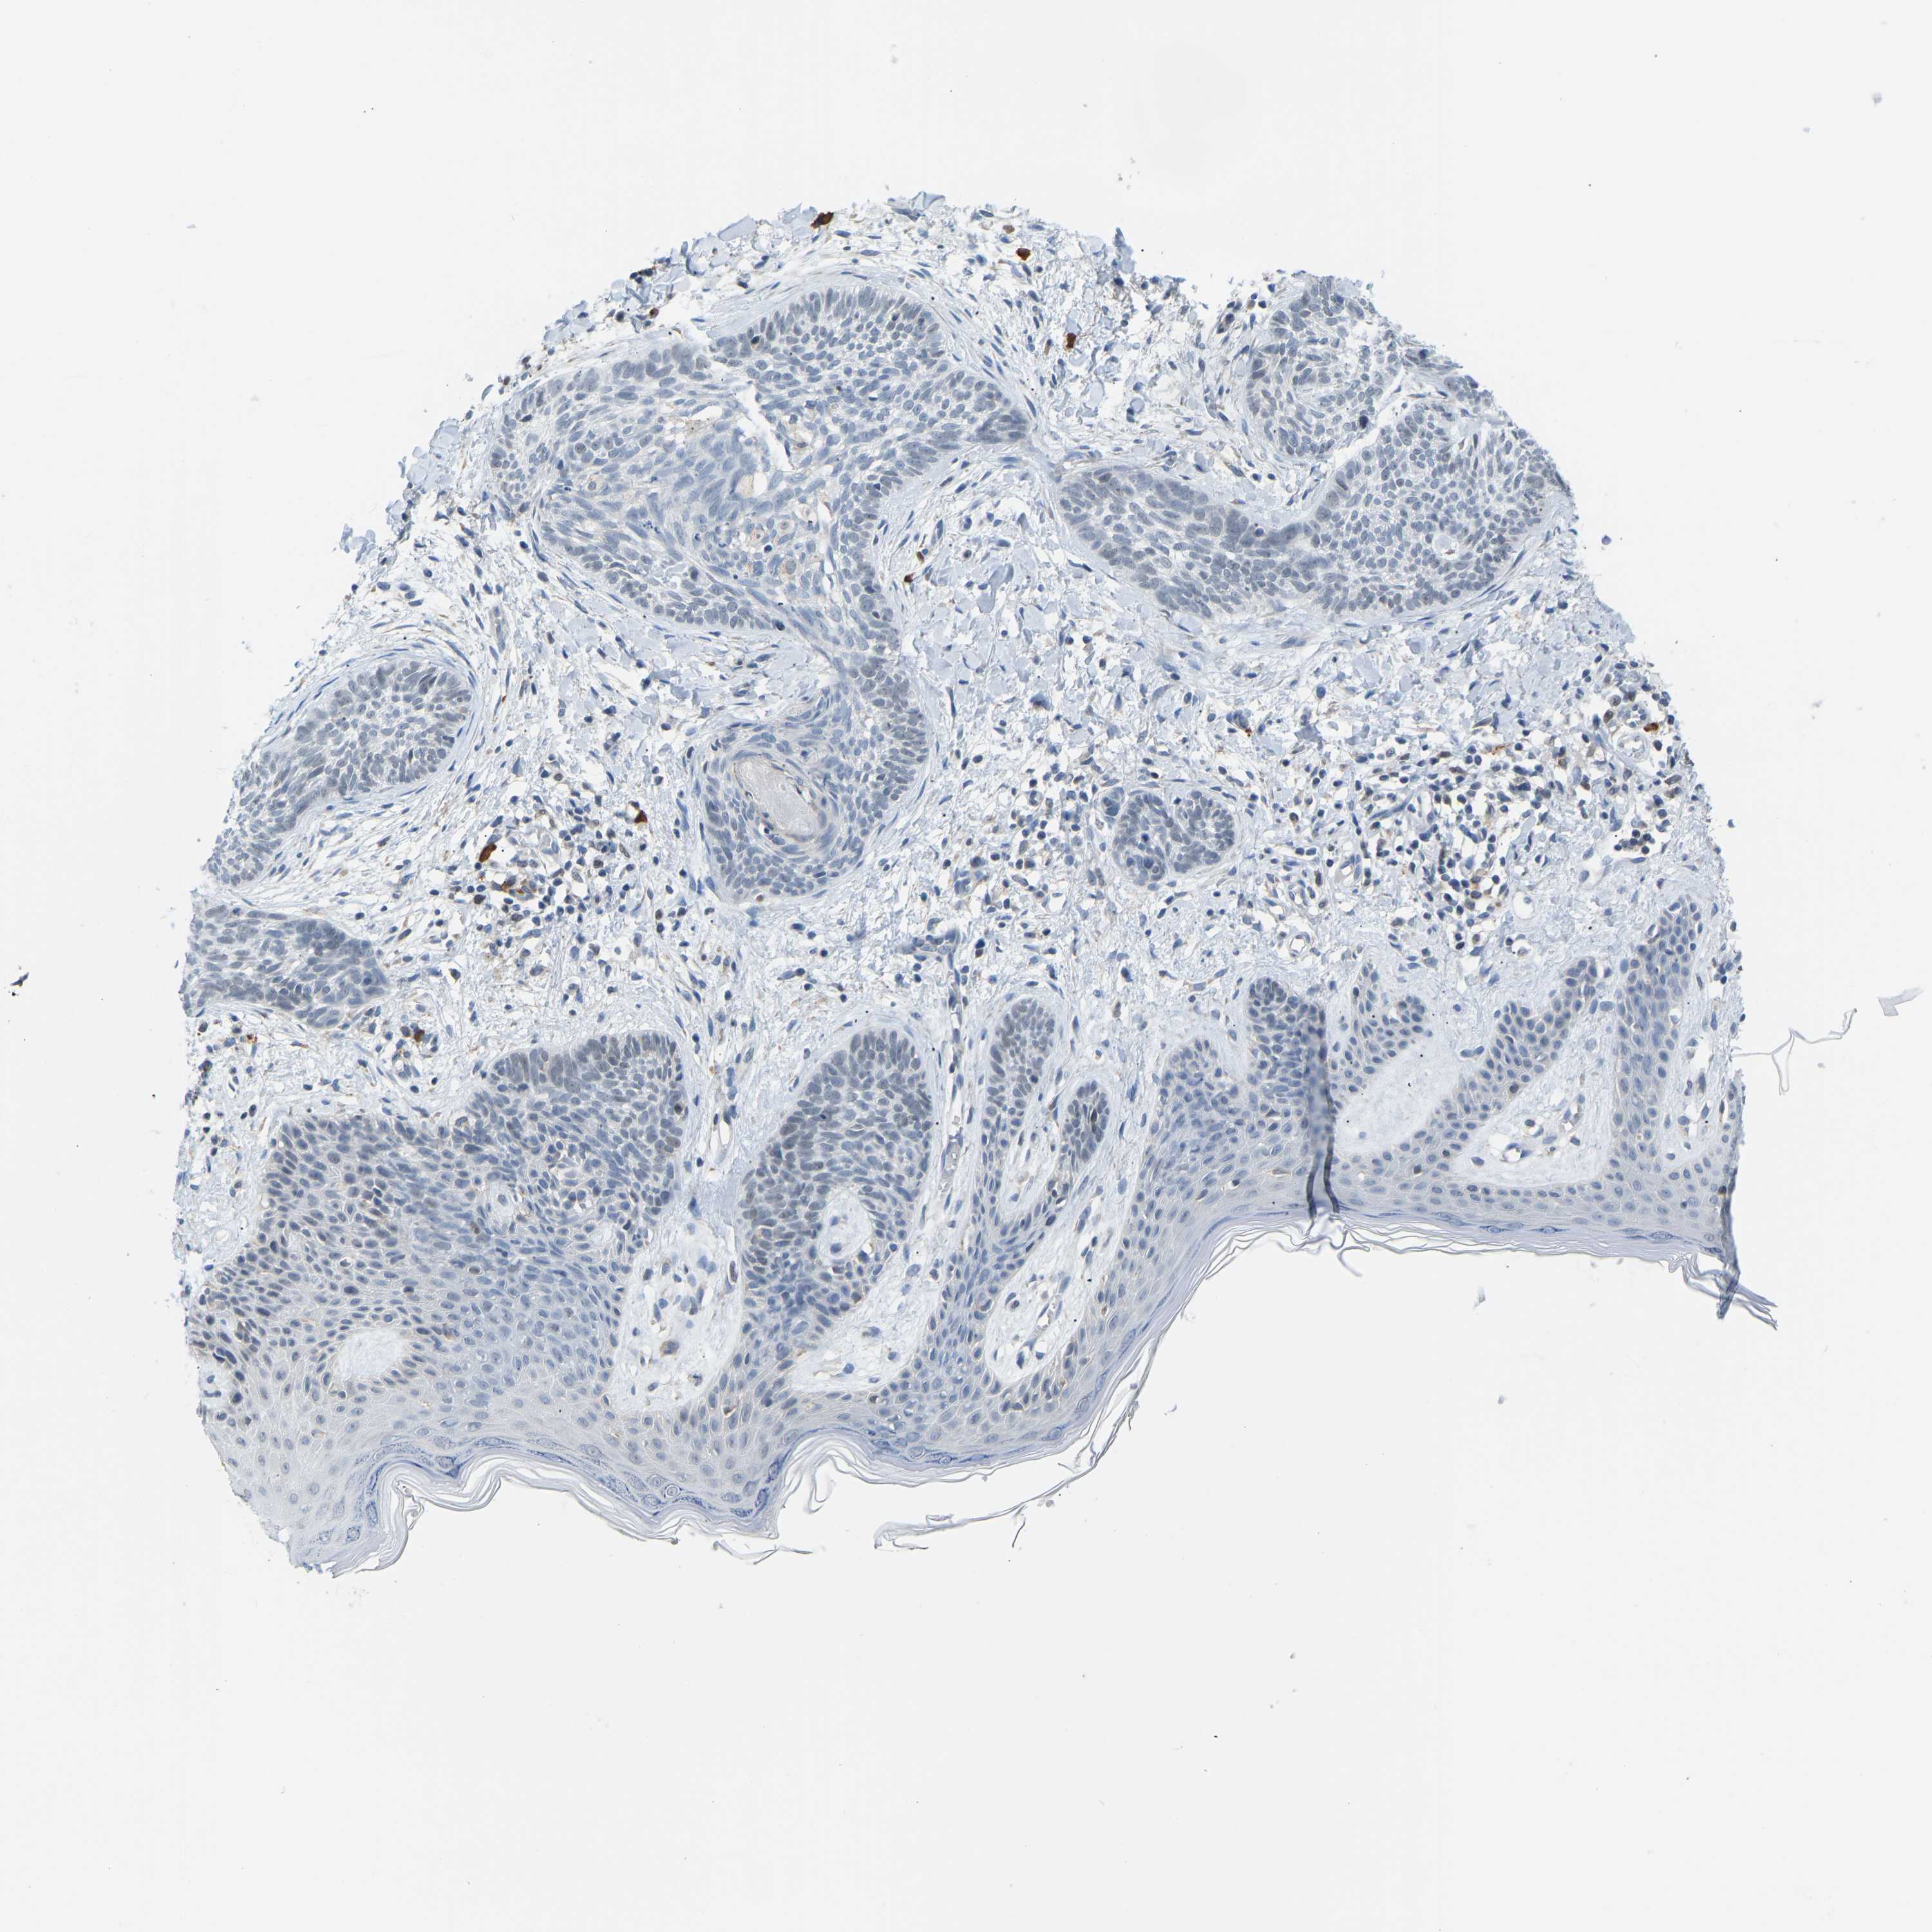

Basal cell and squamous cell cancer

SKIN CANCER - Protein expressioni

A mouse-over function shows sample information and annotation data. Click on an image to view it in a full screen mode. Samples can be filtered based on level of antibody staining by selecting one or several of the following categories: high, medium, low and not detected. The assay and annotation is described here.

Each image is clickable and will lead to virtual microscopy that enables deeper exploration of all samples and also displays staining intensity scores, fraction scores and subcellular localization as well as patient and tissue information for each sample.

Antibody HPA017929

Squamous cell carcinoma in situ, NOS